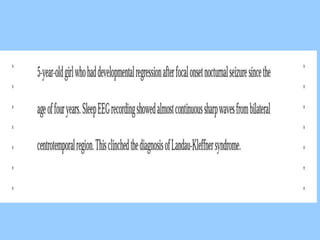

1. The document discusses EEG patterns and findings in various neurological conditions seen in children. It includes descriptions of normal EEG findings as well as abnormal patterns seen in conditions like absence seizures, West syndrome, benign childhood epilepsy with centrotemporal spikes, Lennox-Gastaut syndrome, non-convulsive status epilepticus, subacute sclerosing panencephalitis, and herpes encephalitis.

2. Case studies are presented with clinical histories and EEG findings to illustrate different pathologies. Treatment options are also mentioned for many of the conditions.